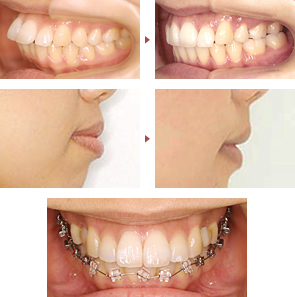

歯列矯正は十人十色!出っ歯(上顎前突)の症例いろいろ

ここで紹介する症例写真は、いずれも出っ歯の治療例です。「出っ歯」と一言でくくっても、程度や仕上がりの希望は患者様によって違うので、治療方法や治療期間は変わります。歯や顎の骨の状態によっては、予測治療期間通りに進行せずに、遅くなったり早まったりすることもあります。是非、初診カウンセリングを受けて、あなたに合った治療法を見つけましょう!

M さん(27歳女性) 予定24ヵ月→実際22ヵ月

第一小臼歯(真ん中から4番目の歯)を、上2本、下2本抜歯して、出っ歯(上顎前突)を治療しました。

治療前後の写真を比較すると、横顔の唇のラインが大きく改善したのがよくわかります。

予測治療期間よりも矯正装置を2カ月早く外すことができて、とても喜んでいらっしゃいました。

選んだ装置は、周囲の人から見えやすい上の歯に「裏側矯正」、見えにくい下の歯に「表側矯正」を使用した、コンビネーション(別名:ハーフリンガル矯正)です。

人に気づかれにくく、かつ、しゃべりやすく違和感が少ない装置を希望する方に合った方法です。